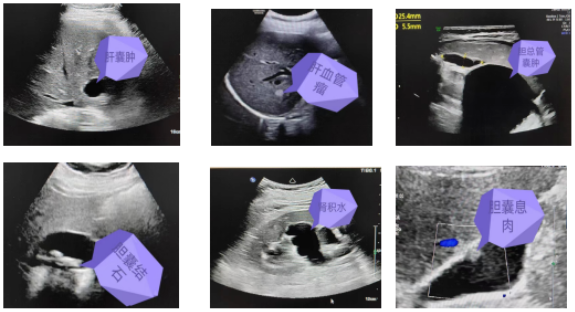

通過彩超檢查可以發(fā)現(xiàn)臟器的形態(tài)大小,有無占位性病變等。常見疾病如肝囊腫、肝血管瘤、膽總管囊腫、膽石癥、膽囊息肉、膽囊炎、肝臟脂肪變性、多脾癥、腎積水、腎結(jié)石、膀胱炎等。部分常見疾病超聲圖像如下:

image